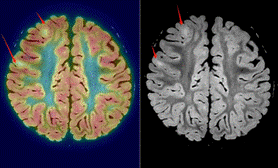

18F-FDG PET:显示发作间期低代谢区域,偶尔也可以抓到发作期的高代谢,可辅助定位致痫区,灵敏度达到85-93%。

图中箭头所示FDG-PET,发作间期低代谢